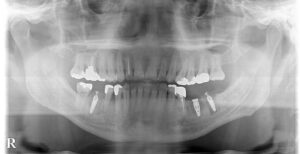

🔶オペ後レントゲン🔶

オペは麻酔医が患者様を眠らせる

じょうみゃくないちんせい法で

オペしたので無痛

2ヶ月後に歯を造ります